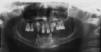

The patient was subjected to initial X-ray assessment, panoramic X-rays were taken as well as maxillary full occlusal computerized X-rays (Figures 2-4). Radiographic assessment revealed multiple tooth ageneses. Additionally to teeth observed at the intra-oral examination, erupting upper canines (right and left) were present, as well as a tooth bud at the level of the first upper left premolar; erupting lower canines were equally present, both with possibility of crown shaped alterations; generalized bone resorption was observed in both arches.

The case here presented exhibited presence of all four upper incisors, with shape alterations, coneshaped teeth, erupting upper canines with apparent cone-shape, upper first premolars and first molars with taurodontia, tooth germ of the second left upper premolar. In the lower jaw presence of lateral coneshaped incisors and erupting lower canines with apparent cone-shape alteration. Severe horizontal bone resorption could also be observed in both jaws.